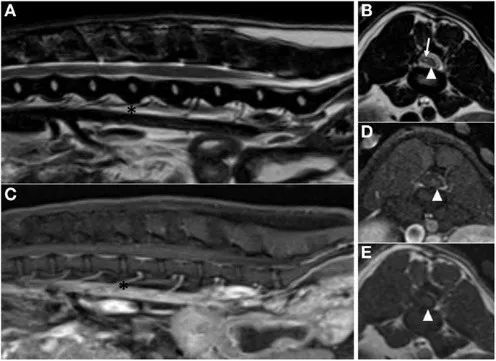

图6 2岁雄性体重477kg约克夏犬术前磁共振图像。矢状面(A)和横切面(B)T2加权图像显示L3-4椎间盘间隙(星号)水平的高信号髓内肿块和肿块颅侧神经水肿(箭头)。矢状面(C)和横切面(D)对比后T1加权图像造影显示肿块明显、均匀的对比增强。

图7图六约克夏术后9个月磁共振图像。(A)状面T2加权图像显示没有瘤周水肿(星号位于L3-4间盘空间的水平)。(B)L3-4稚间盘间隙水平的横断面T2加权图像,显示脊髓萎缩(箭头)。夫状面(C)和横切面(D)对比后T1加权与L3-4椎间盘空间水平的FatSat图像。L3-4椎间盘空间水平的横断面对比前T1加权图像。在所有横断面图像(箭头)上,椎管左侧可见萎缩的脊髓。椎管右侧对比前后T加权横断面图像上的脊髓低信号和T2加权横断面图像上的混合信号物质所占据(箭头)。这表明手木部位脊髓膜粘连的可能性。